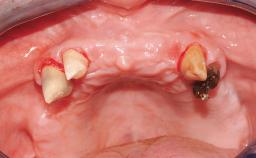

Immediate Loading of Six Implants in the Maxilla and Final Restoration with a Full-Arch CAD/CAM Zirconia FDP

A 63-year-old male patient was referred for a consultation and treatment of partial edentulism in the maxilla. The patient presented with residual anterior teeth and declined a partial removable prosthesis. He reported that the maxillary posterior teeth had been extracted due to mobility and periodontal disease two months before the consultation. The patient’s chief complaint was that his residual maxillary teeth were mobile and that he was unable to chew. The patient’s desire was a stable and comfortable fixed maxillary rehabilitation. The patient was a light smoker (fewer than 10 cigarettes/ day), and his medical history was without significant findings. He was not on any regular medication at the time of consultation. The extraoral examination revealed a normal physiognomy with a correct distribution of the facial thirds. The patient presented a low lip line, and the transition line between teeth and soft tissues was not exposed during a forced smile.

# of Implants 6

Bone Volume Horizontally and vertically sufficient Horizontally deficient Deficient vertically or deficient vertically AND horizontally

Bone Volume Horizontally and vertically sufficient